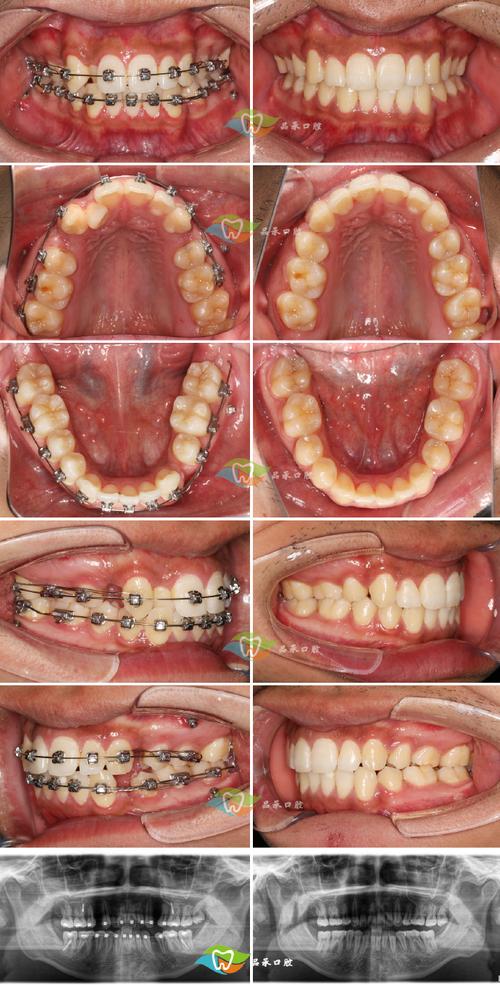

单侧上下拔牙的正畸治疗需系统化操作,流程大致分为五个阶段,第一阶段为术前评估,通过拍摄全景片、头颅侧位片、CBCT及取研究模型,分析牙齿拥挤度、牙根位置、骨量、面部软组织轮廓及咬合情况,特别需关注单侧拔牙后对侧牙齿的代偿潜力及中线纠正的可行性,第二阶段为拔牙设计,通常拔除上下颌同一侧的第一前磨牙(如右侧上下颌4号牙),因其牙根较短、拔牙难度低,且为前磨牙,对咀嚼功能影响相对较小;拔牙后需精确计算拔牙间隙,确保间隙用于解除拥挤、纠正中线及调整咬合,而非单纯内收,第三阶段为矫治器粘接与初始排齐,多选择固定矫治器(如金属托槽或陶瓷托槽)或隐形矫治器,优先排齐拔牙侧及中线的牙齿,建立初步的牙弓形态;此阶段需注意避免对侧牙齿出现不必要的倾斜,防止间隙分布不均,第四阶段为间隙关闭与咬合调整,通过滑动法或关闭曲技术内收拔牙侧牙齿,同时纠正中线偏斜,调整后牙咬合关系,确保单侧拔牙后形成稳定的尖窝交错关系;此阶段需定期调整矫治力,避免牙根吸收或牙槽骨吸收,第五阶段为保持阶段,拆除矫治器后佩戴保持器(通常为 Hawley 保持器或透明保持器),尤其需关注拔牙侧及中线的稳定性,防止复发;保持时间至少2年,期间每3-6个月复诊一次。